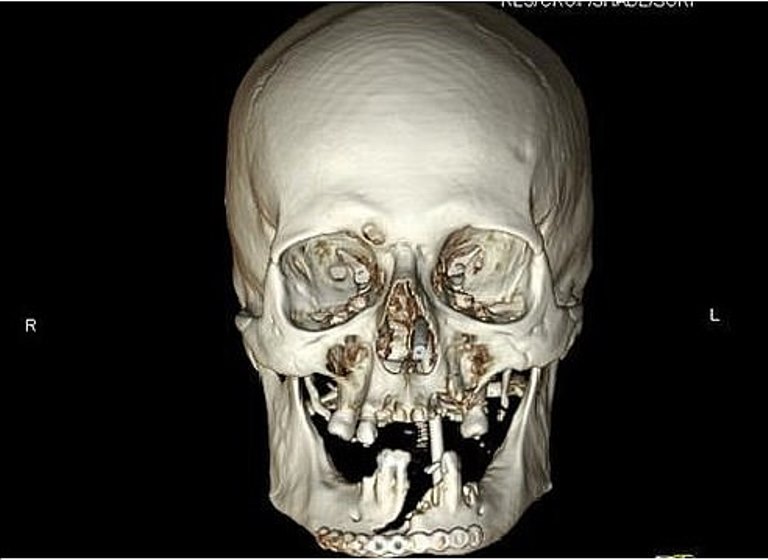

But after a few hours, surgeons were already working to sew his face back together. He accidentally cut his face and tongue in half.

The chainsaw cut through his bottom lip and tongue, tearing his jaw. He pulled a handkerchief from his pocket and kept it to his face but he was quickly losing blood.

A team of surgeons worked on Bill for several hours. His haw had to be fitted with a metal plate and he lost most of his teeth. Nerve damage also left his tongue permanently numb and it took him weeks before he could learn to speak again.

Bill had two more operations to secure his jawline and to prepare his gums for a new set of teeth. He said that the worst thing about it is that it has changed his diet.